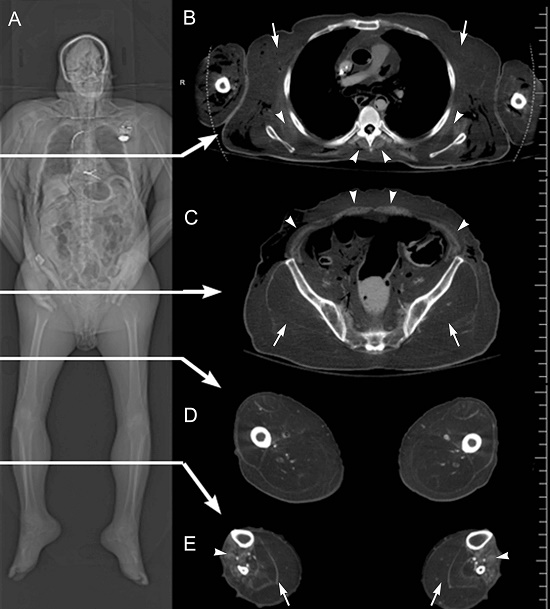

Prior to dissection, a full-body CT scan was obtained in one helical acquisition using a Siemens (Munich, Germany) Somatom Definition Flash CT scanner. Slice thickness was 0.6 mm, kV 140, and mA 280. Axial, sagittal, and coronal images were reconstructed with 5.0 mm slice thickness. The frontal CT image (Figure 3) revealed dispersed replacement of skeletal muscle with fat-density tissue. An axial CT image at the mid-chest level shows profound muscle loss in the region of the pectoral muscles but partial sparing of the serratus anterior and paraspinal muscles. The axial CT image at mid-pelvic level reveals fat replacement of the gluteal muscles with partial sparing of the musculature of the abdominal wall. The axial CT image at mid-thigh level indicates fatty replacement of the musculature in all compartments (anterior, posterior, and medial). Finally, the axial CT image at the mid-calf level depicts the extensive replacement of the posterior compartment musculature but partial sparing of the anterior compartment. Overall, the CT images indicate the selective but pervasive replacement of skeletal muscle with fat-density tissue, most prominently in areas of the proximal appendicular skeleton of the pectoral and gluteal regions.